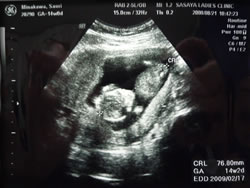

9月4日:妊婦検診・・・オナカの赤ちゃん(96mm)

約1ケ月で 倍の大きさになった ベビちゃん。

それとあわせて あちしも。。。大きく(なりすぎ)なっちゃって、ついに、今日、

「体重コントロール 上手にしましょう・・・」とダメダシ! ・・・

オナカの赤ちゃん・・

うーん、 がんばろう 大きくなぁれ。 大きくなぁれ。

あたしの赤ちゃん。